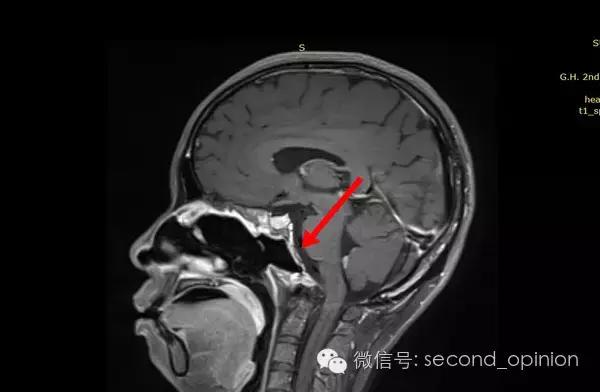

2014年9月1日MRI(手术治疗前)

质子治疗前

2015年1月25日 对比质子治疗之前增强核磁共振影像无明显变化,脊索瘤放疗后变化缓慢,建议3月后继续复查。

2015年04月01日 对比增强核磁共振影像,同第一次复查。

2015年06月03日 对比增强核磁共振影像,对比第三次复查,肿瘤略有缩小。

质子治疗后第四次复查

目前患者生活质量良好,无复发转移。